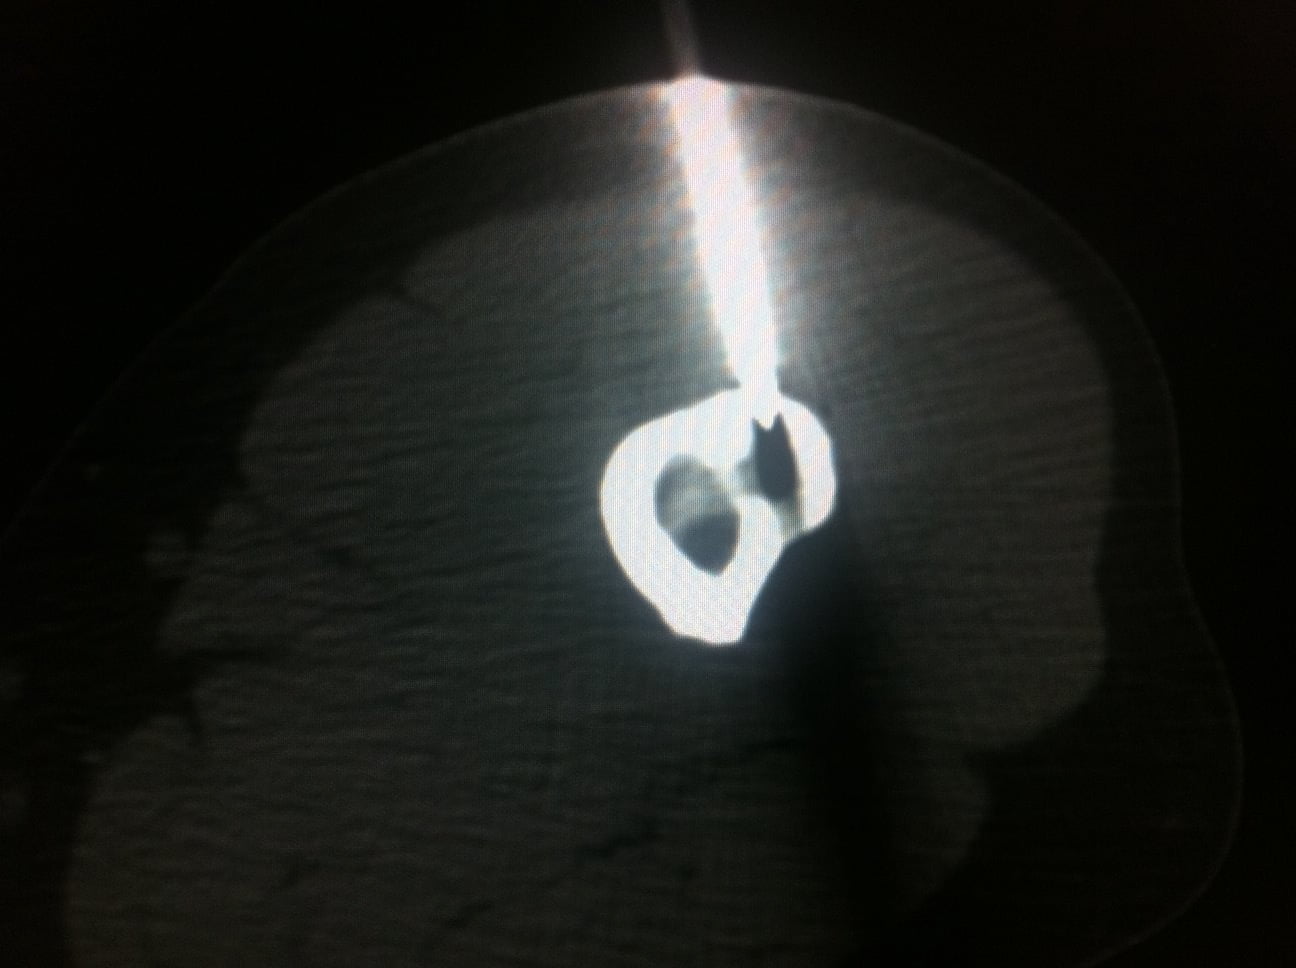

Sous guidage scopique et scanner un trocart 11 gauges coaxial Thiebaud t’AM est introduit dans la tumeur. Le contrôle itératif par scanner permet de positionner au plus près le matériel. Cette technique évite une ouverture cutanée mais surtout permet de conserver la structure osseuse adjacente et s’assure d’une précision optimale.

Nous réalisons la Mise en place d’une sonde de RF de 1mm au centre du nidus puis Ablation par RF à 90° pendant 4 à 5 mn